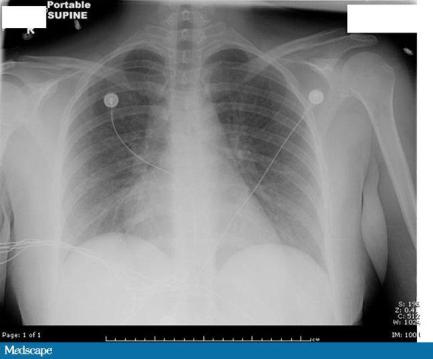

▎輔助檢查:血常規(guī)示白細胞計數(shù)31.6*109/L,中性粒細胞百分比13%。血清肌酐2.4 mg/dL(211.2 μmol/L)。動脈血氣分析示二氧化碳分壓(PCO2 )27 mmHg,氧分壓(PO2 )56 mmHg,HCO3- 19 mmol/L,BE 4.4 mmol/L(正常范圍0-2 mmol/L)。尿液分析、宮頸分泌物革蘭染色、胺臭味試驗均陰性。胸片符合急性呼吸窘迫綜合征(ARDS)的表現(xiàn)。